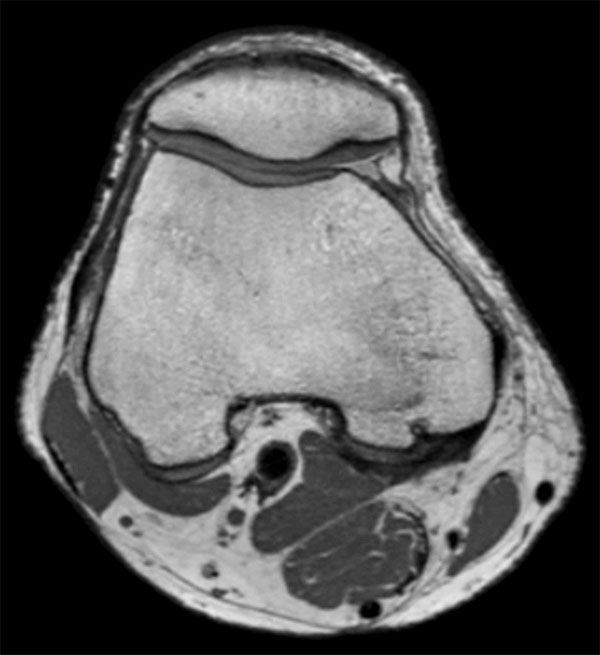

Comprehensive 3D knee imaging with MSK VIEW